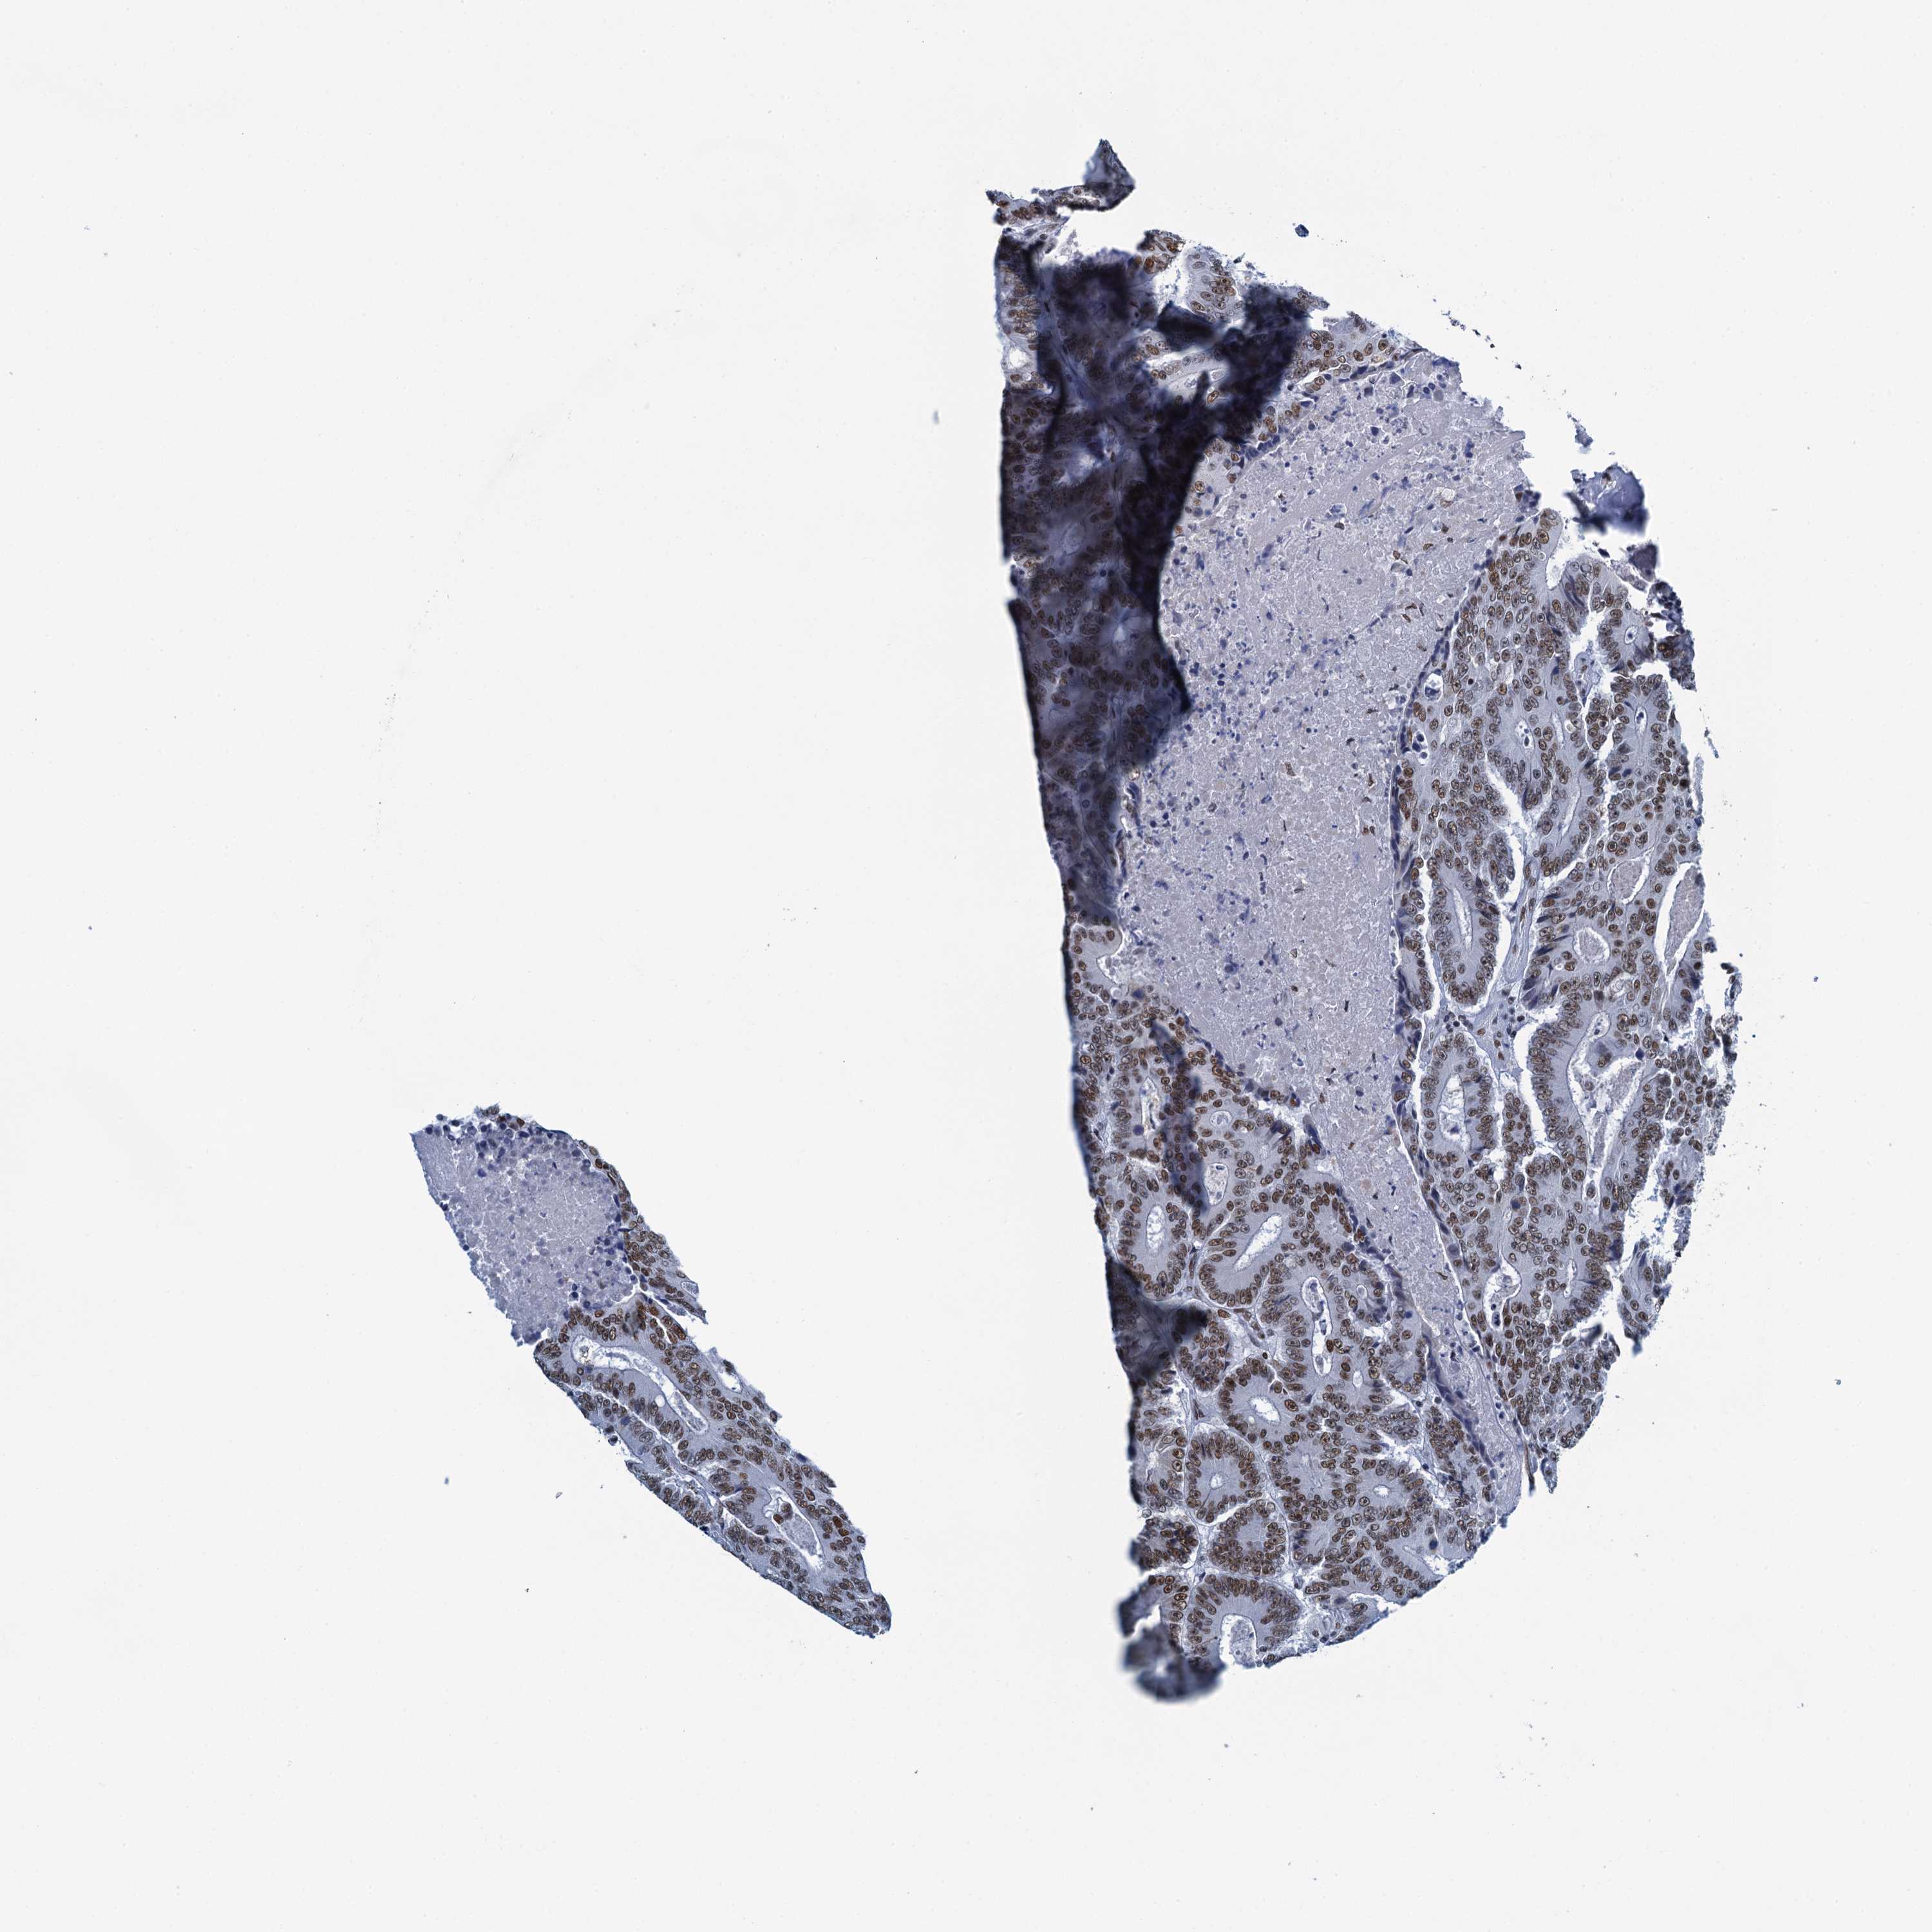

CANCER COLORECTAL CANCER Show tissue menu

Colorectal cancer

Human cancer

Colon adenocarcinoma